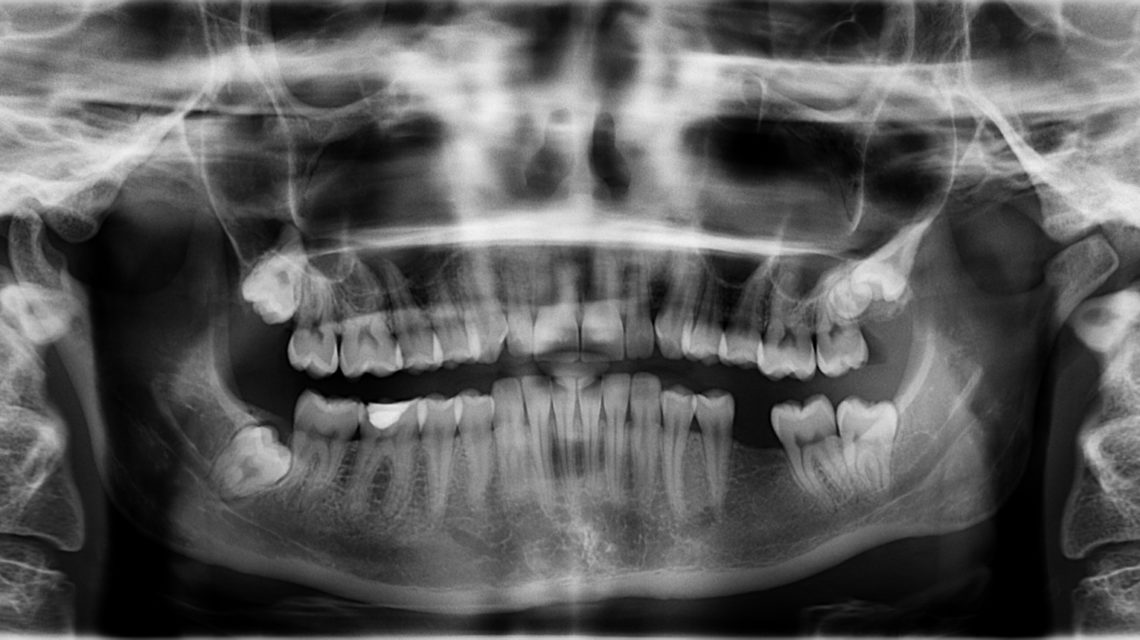

WebA differenza di quelle intraorali, la panoramica dentale è una radiografia extraorale, ovvero in cui l'apparecchio che produce le immagini e la lastra sono posizionati fuori dalla bocca.. WebLa radiografia panoramica delle arcate dentarie (OPT), permette la visualizzazione e la valutazione delle strutture dentali, ossee e articolari all’interno. WebPanoramica, detta anche ortopantomografia. Permette la visione completa delle ossa mascellari, dei denti, della zona nasale e delle articolazione temporo.

WebPanoramica, detta anche ortopantomografia. Permette la visione completa delle ossa mascellari, dei denti, della zona nasale e delle articolazione temporo. WebLa panoramica dentale è uno strumento diagnostico di fondamentale importanza nel caso di: Valutazione odontoiatrica prima e dopo interventi di tipo implantologico. Studio dei denti. WebL’ ortopantomografia (OPT), chiamata anche radiografia panoramica delle arcate dentarie, è una tecnica radiografica che produce un’ immagine dei denti, delle arcate dentarie e. WebL’ortopantomografia è comunemente nota con il nome di panoramica dentale o radiografia panoramica delle arcate dentarie. Questo esame si effettua con uno strumento detto. WebIn linea di massima, però, possiamo dire che i prezzi di una panoramica dentale sono abbastanza contenuti. Infatti possono partire da un costo base di 25 euro. WebLa panoramica dentale, detta anche ortopantomografia, è un esame radiologico che permette di ottenere un’immagine dei denti, delle arcate dentarie e delle ossa mascellari. WebL’ortopantomografia si esegue per lo studio panoramico dei denti, degli alveoli dentari, della mandibola e del mascellare superiore. E' fondamentale per un bilancio. WebL’ortopanoramica è una macchina che consente di ottenere una radiografia dentale e di effettuare una diagnosi precisa e sicura. E’ un apparecchio radiografico che produce su. WebL’ortopanoramica dentale è il primo esame che si esegue per osservare l’eruzione e la crescita dei denti del giudizio. In caso di denti da estrarre, come primo.